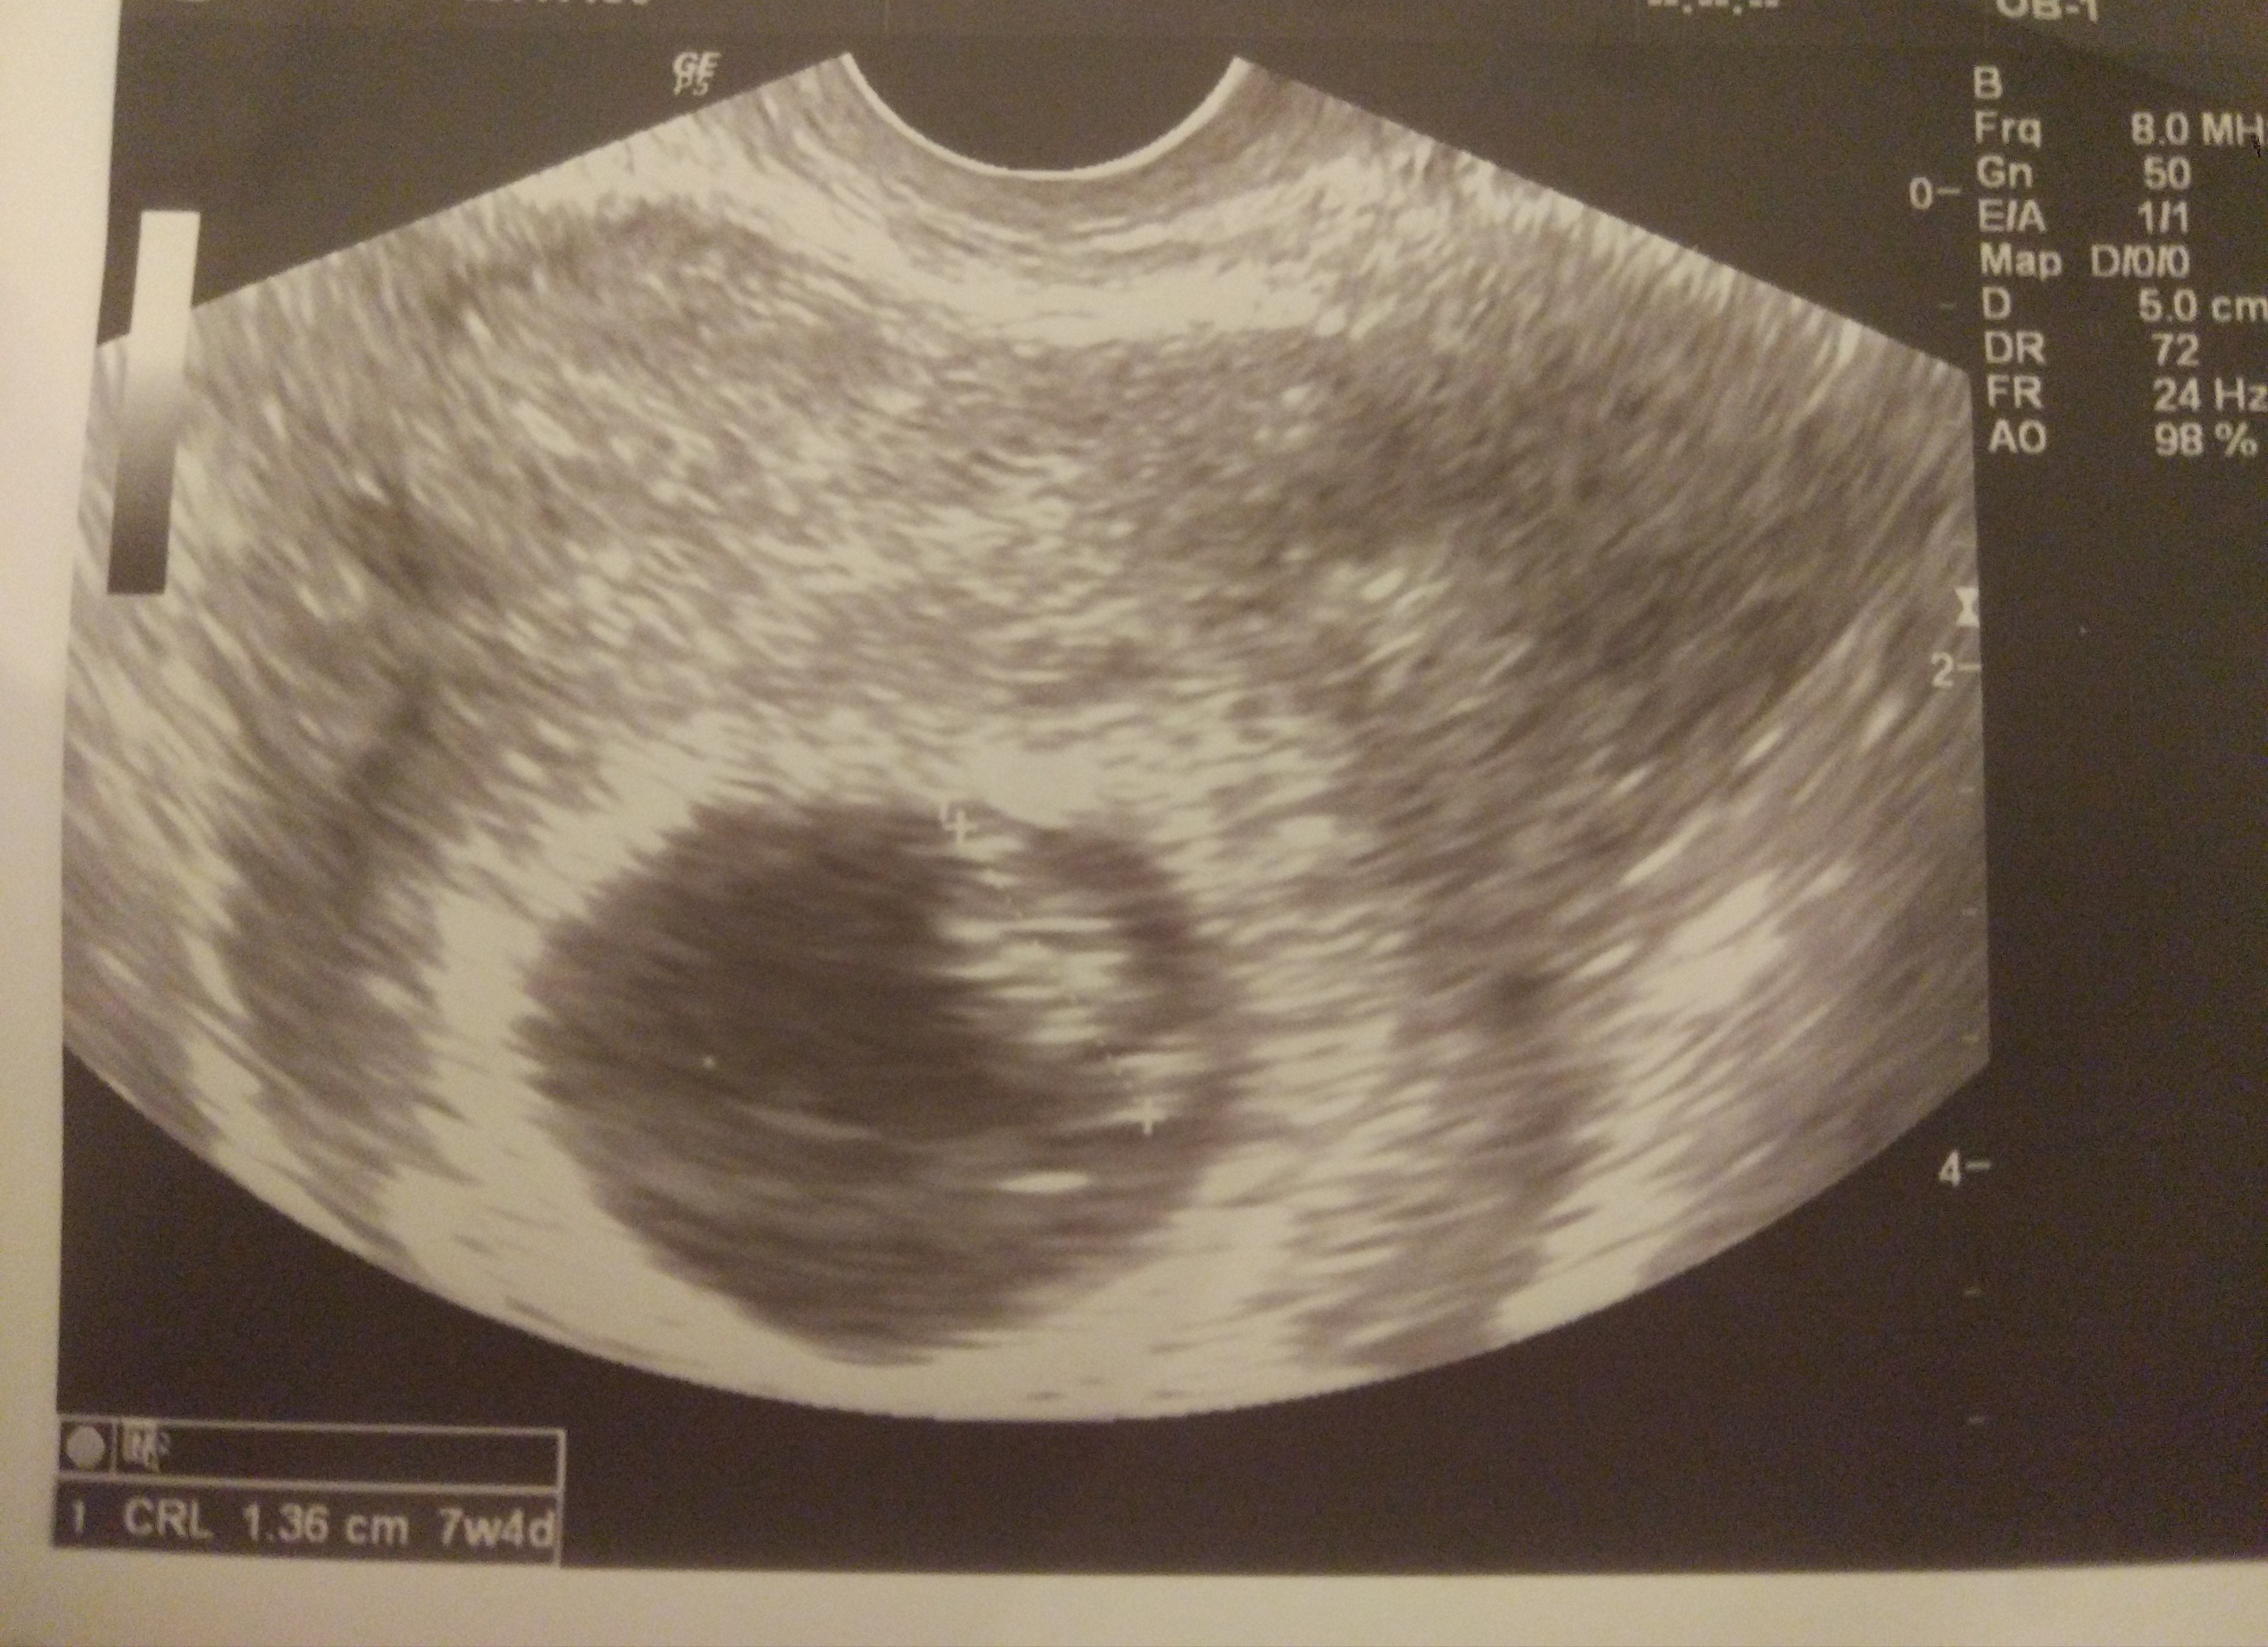

Za wiele nie widać na tej jakości USG, ale i tak fasolka jest cudna 😍

Załączniki

• IMG_20200224_172319.jpg

IMG_20200224_172319.jpg

2,5 MB · Wyświetleń: 122